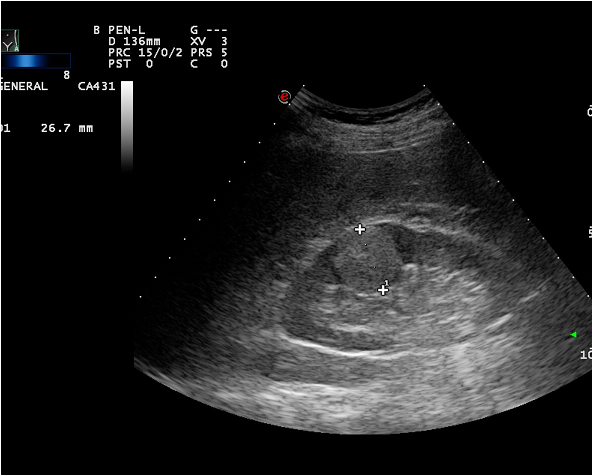

Image

Figure 3. Kidney tumor on US

Ultrasonography (US), which is an extensively used and a widely available method, is often the first step in the diagnostic work up. During a regular abdominal US scan both kidneys are examined. Sensitivity of the US examination is significantly lower than of a CT scan, still important clinical questions can be answered with this technique. When a tumor is visualized, it is usually a hypoechoic, relatively well circumscribed mass.

Diagnostics of cystic lesions is based on the Bosniak classification system, which categorizes cystic lesions by their density, calcifications, wall thickness, contrast enhancement, surface lobulation and characteristics of the cyst contents.